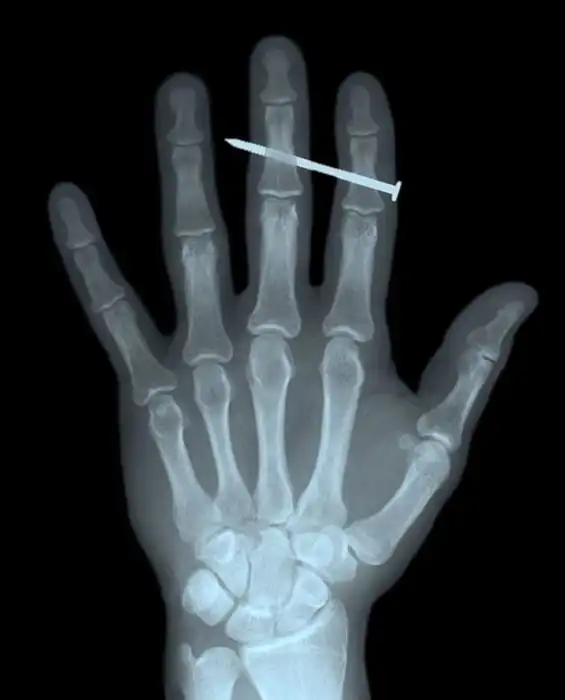

Картинка с гвоздем в средней фаланге третьего пальца кисти похож на подделку, но кто знает может забил гвоздь по мягким тканям.